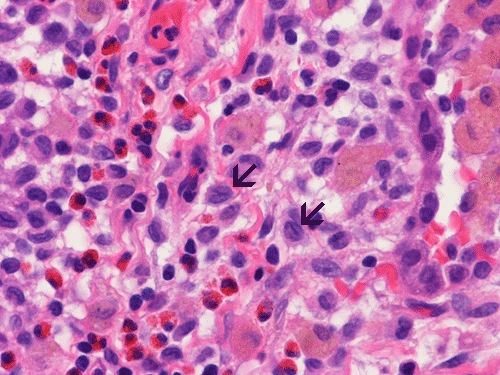

At scanning magnification (Panel A), the lung parenchyma is replaced by some coalescing fibrous nodules. The degree of involvement is variable at different fragments (Panel B and C). In the less affected areas, there are some fibrotic thickening of the septa (Panel C). In some areas, the changes are minimal and the pleural appear to be uninvolved (Panel D and E). In low to medium magnifications, these nodules of fibrosis contains a large number of hemosiderin laden macrophages (Panel F and G) admixed with fibrous tissue. The diagnostic tissue, however, is present in areas with increased cellularity. In these areas, there is a background of cells with a moderate amount of cytoplasm and bland nuclei. Some of these nuclei have kidney shape (arrow in Panel H). In some areas, many of the nuclei have a deep nuclear groove that resemble a coffee bean (arrow in Panel I). In the third type of areas, the nuclear grooving is not distinct (Panel J). Prominent eosinophilic infiltrations are almost always present. Immunohistochemistry on CD1a revealed many positive cells (Panel L). Also present in the specimen are multiple small blood vessels with thickened intima (Panel K). A Movat pentachrome stain demonstrates an internal elastic layer in these vessels and confirms that these are arteries (Panel M and N).

Histopathologic signature of Langerhans cell histiocytosis, namely kidney shaped or coffee bean shaped, bland nuclei associated with eosinophilic infiltration is not difficult to see in most of the cases. The amount of eosinophilic infiltration and the proportion of cells with nuclear grooving, however, can be quite variable but this problem can usually be overcome by a diligent search. Demonstration of CD1a by immuhonistochemistry or Birbeck granules by electron microscopy will confirm the diagnosis.

Pathologically, PLCH can be broadly divided into an early or cellular stage and a late or fibrotic stage. Demonstration of LCs is of critical importance for a correct diagnosis. The morphology of LCs is similar to LCH in other organs. LCs are characterized by a deep nuclear groove which lead to “coffee bean-shaped” or “kidney-shaped” nuclei. In most cases, the level of atypia and pleomorphism is low. A moderate amount of amphophilic to weakly eosinophilic cytoplasm is present. The cytoplasmic membrane is indistinct. Eosinophils and chronic inflammatory cells, varying from scant to abundant, are present. Except for a scant frankly pleomorphic cases, the level of pleomorphism and atypia is minimal to low. Eosinophilic abscesses with central necrosis may be present. Immunohistochemically, LCs are similar to their normal counter parts and are positive for CD1a and S100. At the ultrastructural level, Birbeck granules can be demonstrated. For most cases, the diagnosis can be established by histopathologic criteria but these additional features help to confirm the diagnosis.